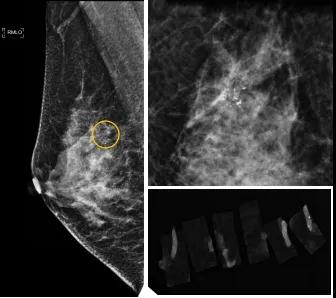

46歲的某女士在西安國際醫(yī)學(xué)中心醫(yī)院體檢時(shí),行乳腺X線攝影(俗稱鉬靶)發(fā)現(xiàn)右乳可疑簇狀鈣化,分布范圍不到1厘米,臨床觸不到,超聲很難發(fā)現(xiàn),但是這種鈣化風(fēng)險(xiǎn)比較高,依據(jù)國際BI-RADS指南需要明確病理!

西安國際醫(yī)學(xué)中心醫(yī)院影像診療中心陳寶瑩副主任帶領(lǐng)的團(tuán)隊(duì),采用全數(shù)字化乳腺X線三維立體定位系統(tǒng)可實(shí)施。這個(gè)團(tuán)隊(duì)的成員大部分來自知名三甲醫(yī)院,有著十余年影像引導(dǎo)下乳腺介入診療的經(jīng)驗(yàn),X線引導(dǎo)穿刺定位和活檢例數(shù)居西北前列。為減少患者創(chuàng)傷,在詳細(xì)判讀了患者資料,并與患者及甲乳外科劉曉敏主任充分溝通的基礎(chǔ)上,團(tuán)隊(duì)確定采用全數(shù)字化乳腺X線三維立體定位系統(tǒng)下實(shí)施粗針活檢。

當(dāng)天,乳腺X線三維立體定位系統(tǒng)清晰顯示出了所有鈣化。為了獲取充足的組織量,保證病理診斷的準(zhǔn)確性,團(tuán)隊(duì)選用14G穿刺針并多點(diǎn)、多角度取材,組織取出后,又立即在高清標(biāo)本攝影系統(tǒng)中進(jìn)行投照,從而確定了取出組織中具有足夠的可疑鈣化。整個(gè)過程患者無任何不適,活檢結(jié)束后即回家觀察。